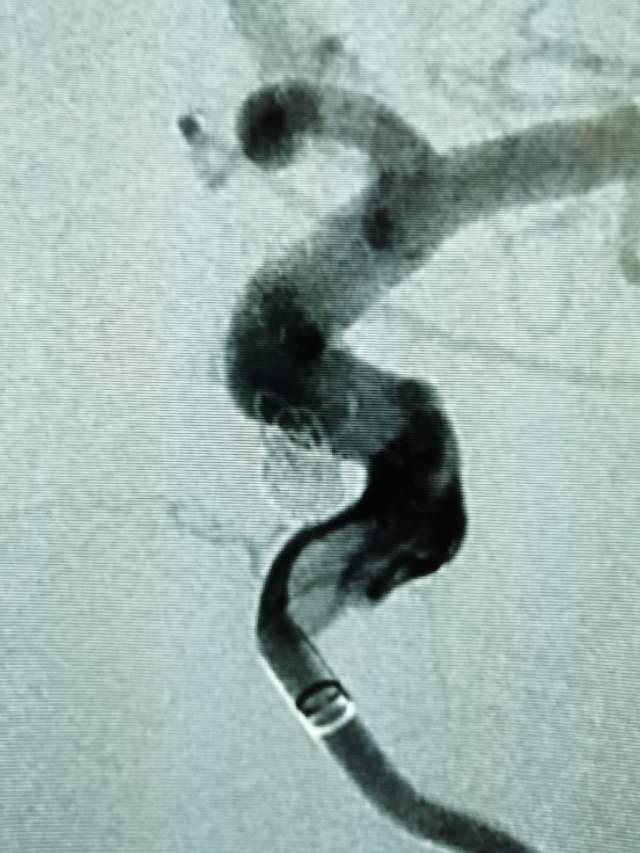

Jailing技术治疗床突旁未破裂动脉瘤